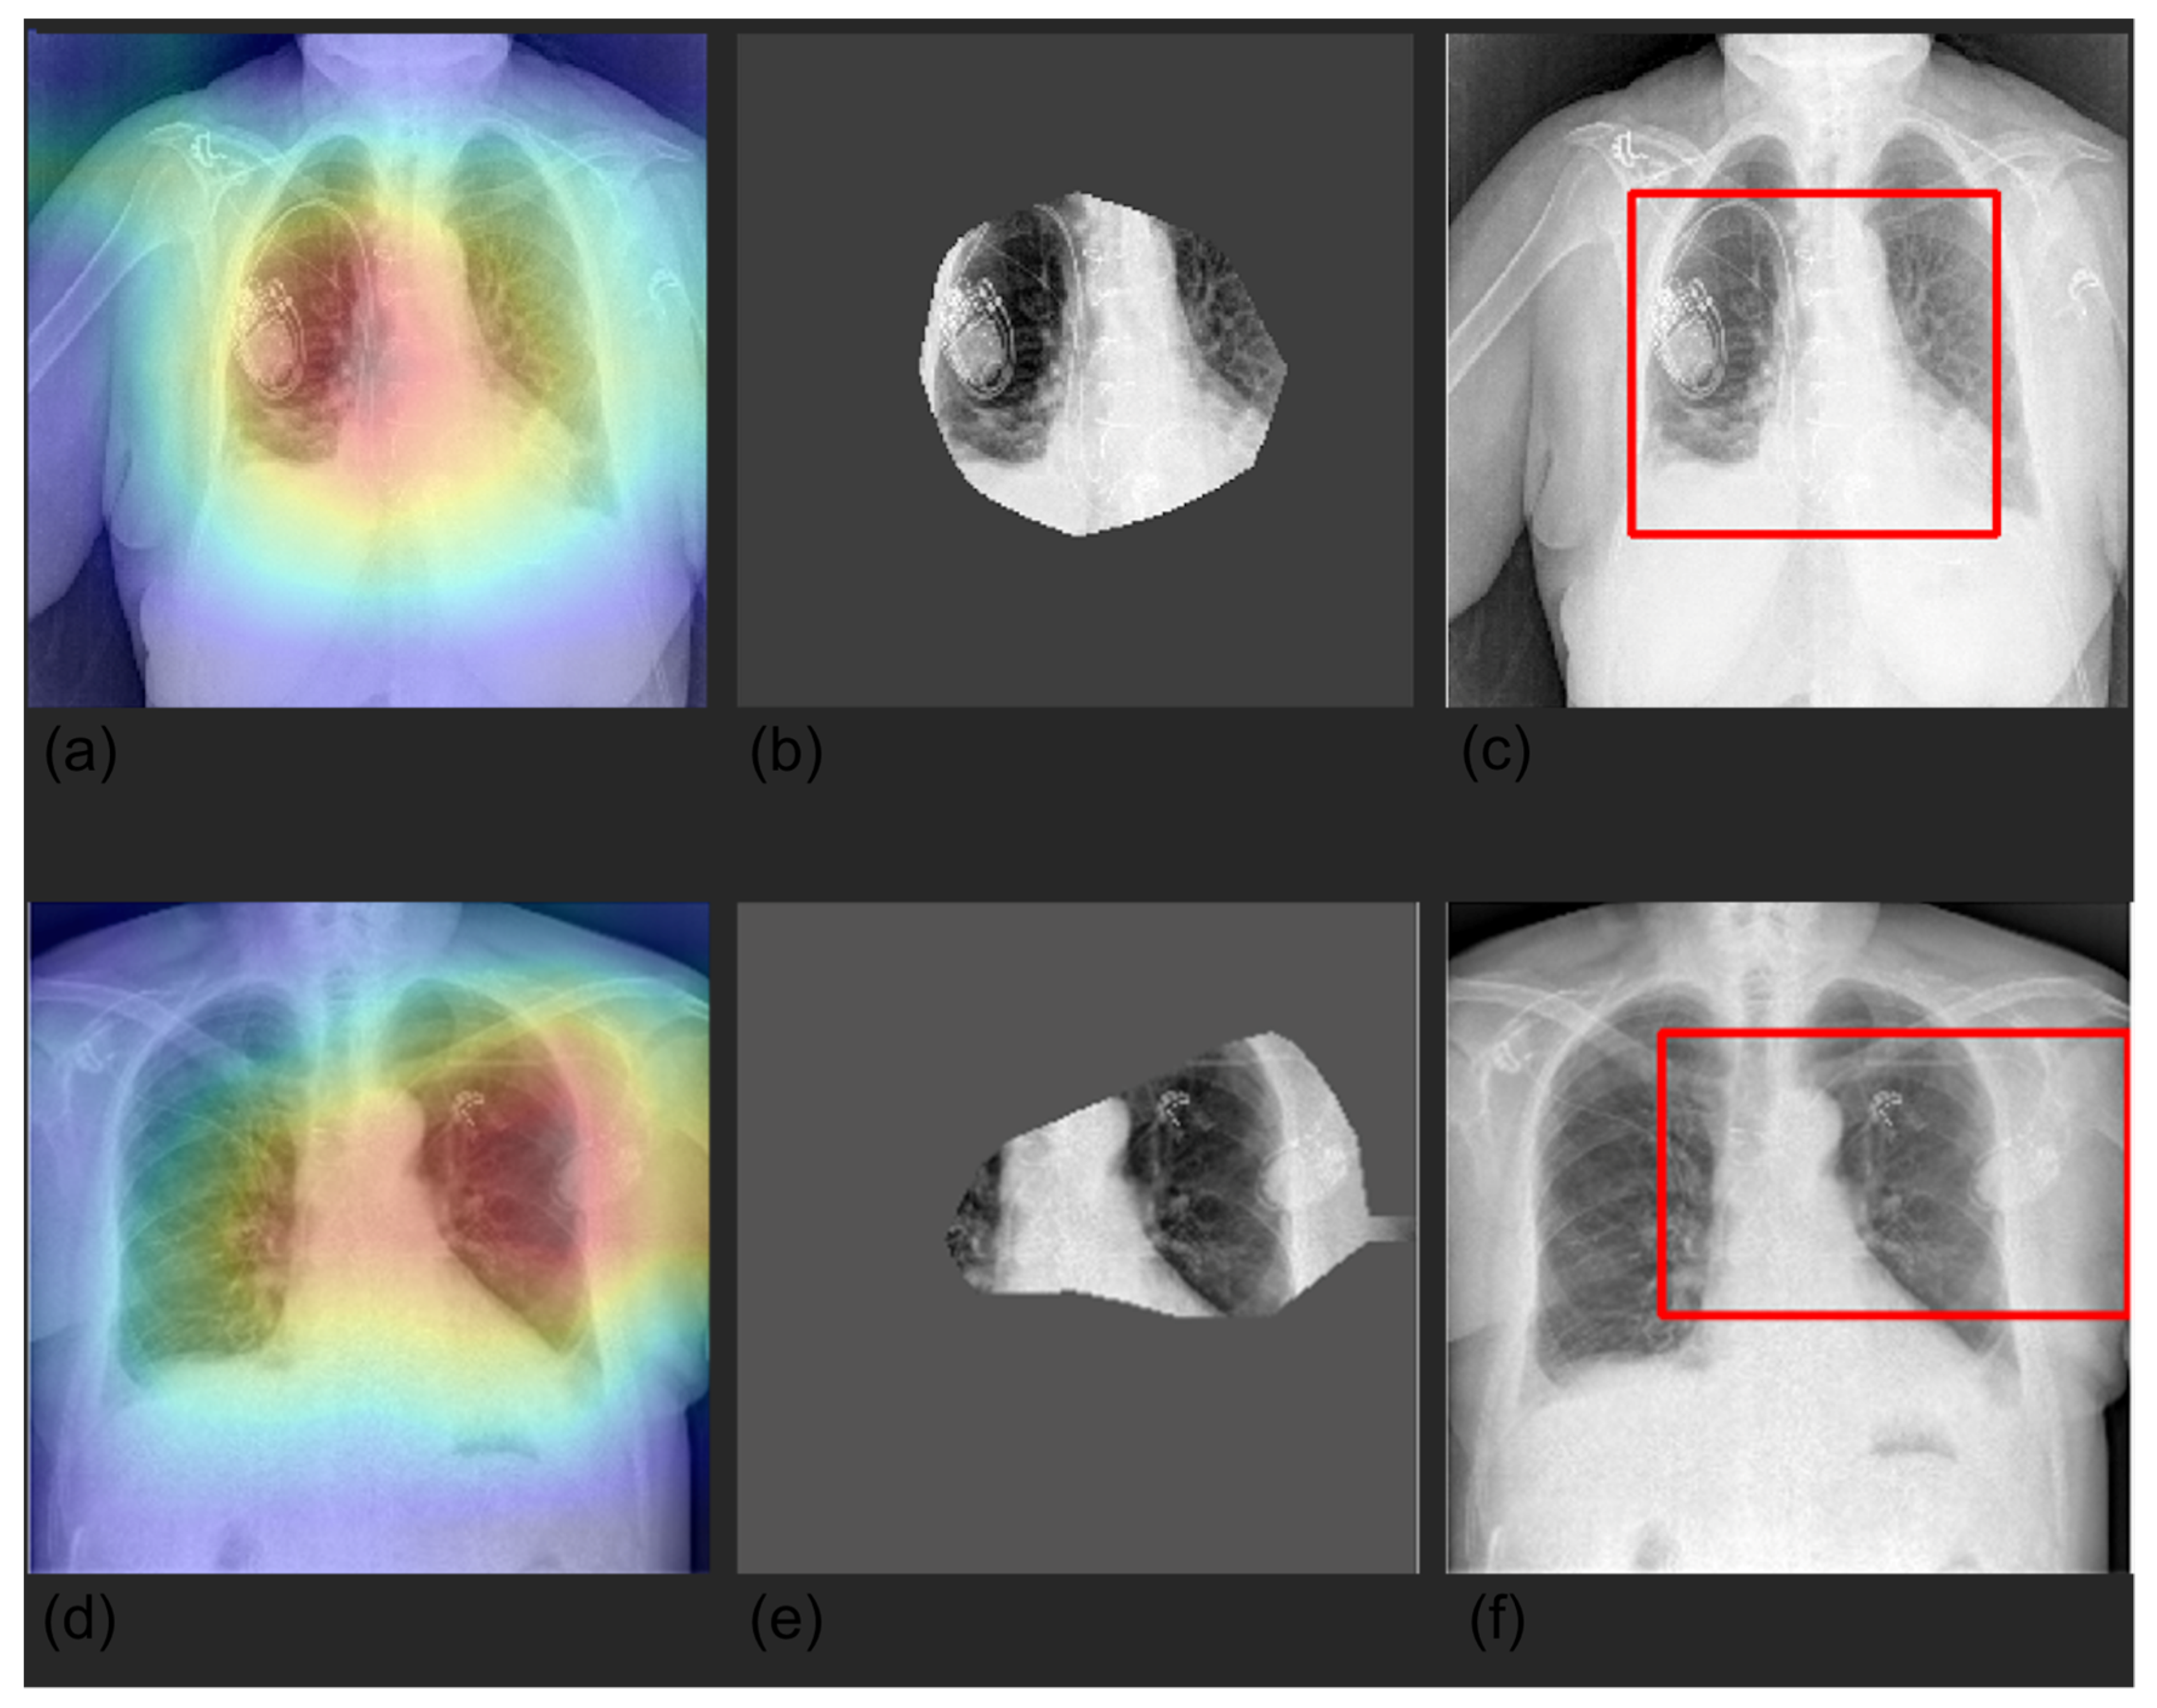

2.5. Explainability

3.4. Grad-CAM